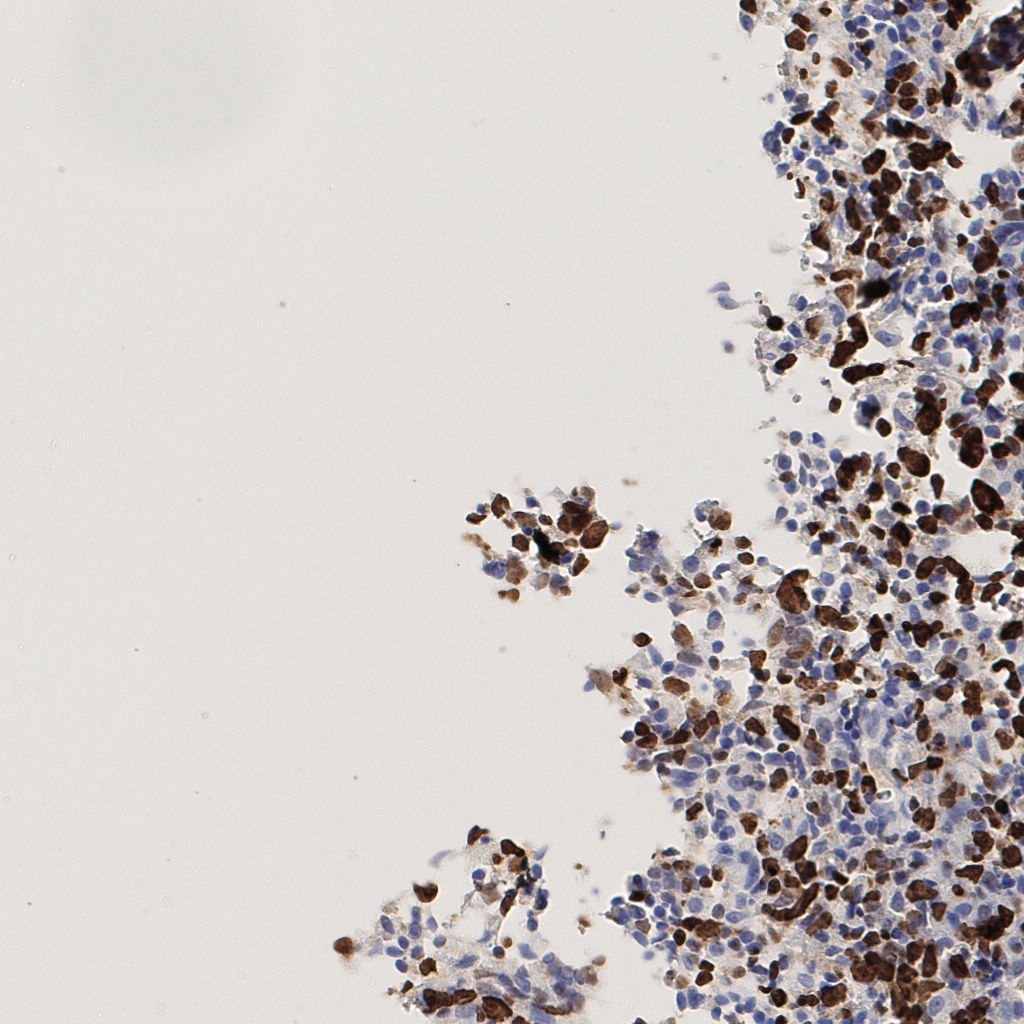

7.85%

Ki67 指数

阴 1104 阳 94

切片统计

总切片 1953

有效 288

已标记 288

有效率 15%